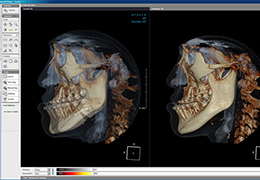

High-quality and fast 3D reconstruction and 3D rendering

Performs 3D reconstruction and volume rendering.

Side-by-side comparative assessment for pre- and post-operative scans.